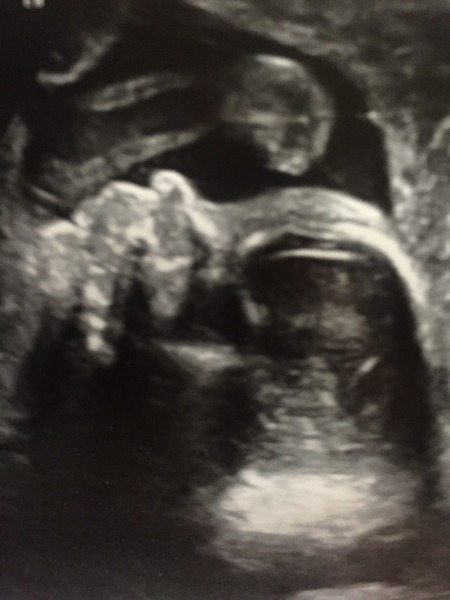

Scan was sooooo emotional, I've finally managed to stop blubbing. I can't believe this might actually be going to happen. A very wriggly baby measured 2 days ahead of my dates Grin